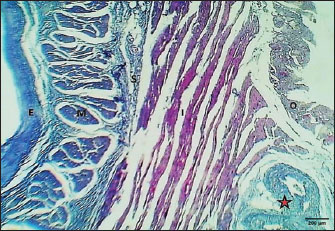

Fig. 15. Cross-section of esophagus: abdominal region (mature cat) shows (E) very thick epithelium, (M) thick muscularis mucosa, (S) submucosa, (I) inner circular layer, and (O) outer layer of smooth muscle of tunica muscularis. Masson’s trichrome stain.

The results revealed that the cervical segment’s mucosa was very thick, with many mucosal folds covered by slightly thick non-keratinized stratified squamous epithelium with marked parakeratosis (Figs. 7 and 8). Lamina propria submucosa revealed the absence of the muscularis mucosa, which comprised dense, irregular, collagenous connective tissue rich with blood vessels (Figs. 8 and 9). Muscularis externa of the esophagus at the chest segment is composed of thickened circularly oriented bundles and longitudinally oriented bundles of skeletal muscle fibers (Fig. 10). At the chest segment, the esophagus also showed many huge folds, and the epithelium was similar to that of the cervical segment (Fig. 11). The lamina propria comprised slightly thick fibrous tissue separated from the tunica submucosa by 3–4 layers of interrupted circular smooth muscle fibers of the muscularis mucosa (Fig. 12). The tumor submucosa consisted of thick layers of non-glandular highly vascular fibrous connective tissue (Fig. 12). Tunica muscularis of the thoracic region was continuing that in the cervical segment. The esophagus in the abdominal region was similar to that observed in the thoracic segment (Fig. 13). The lamina propria was built up by dense collagenous connective tissue separated by very thick longitudinal and circular layers of smooth myofibers (muscularis mucosa) (Figs. 14 and 15). The muscularis externa comprised a very thick circular bundle and a thin longitudinal bundle of smooth myofibers (Fig. 15). The histometric results revealed significant differences in the height of mucosal folds in the chest and abdominal segments, whereas the fold thickness was significantly increased in the abdominal region. The thickness of the muscularis externa revealed no significant differences in the chest and abdominal regions. The epithelium height was significantly reduced in the abdominal region (Table 3).